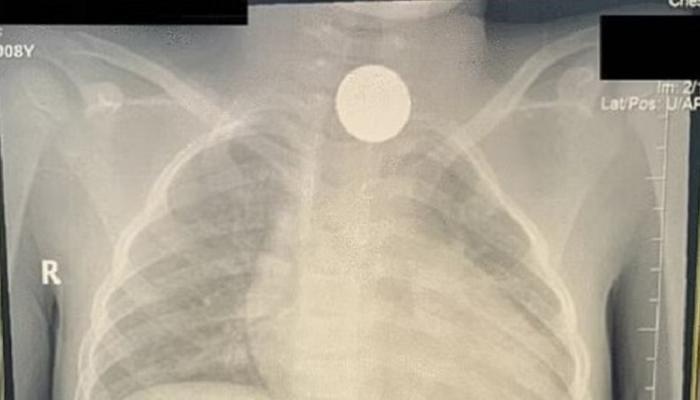

السعودية..عملة معدنية ظلت عالقة بمريء طفلة 4 سنوات.. اكتشفت بالصدفة

2022-08-21